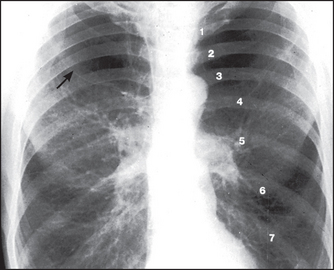

Figure 12.12 Emphysema The lungs are overinflated with low, flat hemidiaphragms. The level of the hemidiaphragms is well below the anterior aspects of the sixth ribs. The diaphragm normally projects over the sixth rib anteriorly and the tenth intercostal space posteriorly. Count the ribs anteriorly (1–6). There is increased translucency of both upper zones with loss of the vascular markings due to bulla formation (arrow). This increased translucency is not due to overexposure. The hila are prominent because of the enlarged central pulmonary arteries. In contrast, the smaller peripheral pulmonary arteries (the lung markings) are decreased in size and number. This is due to actual destruction, displacement around bullae and decreased perfusion through emphysematous areas.